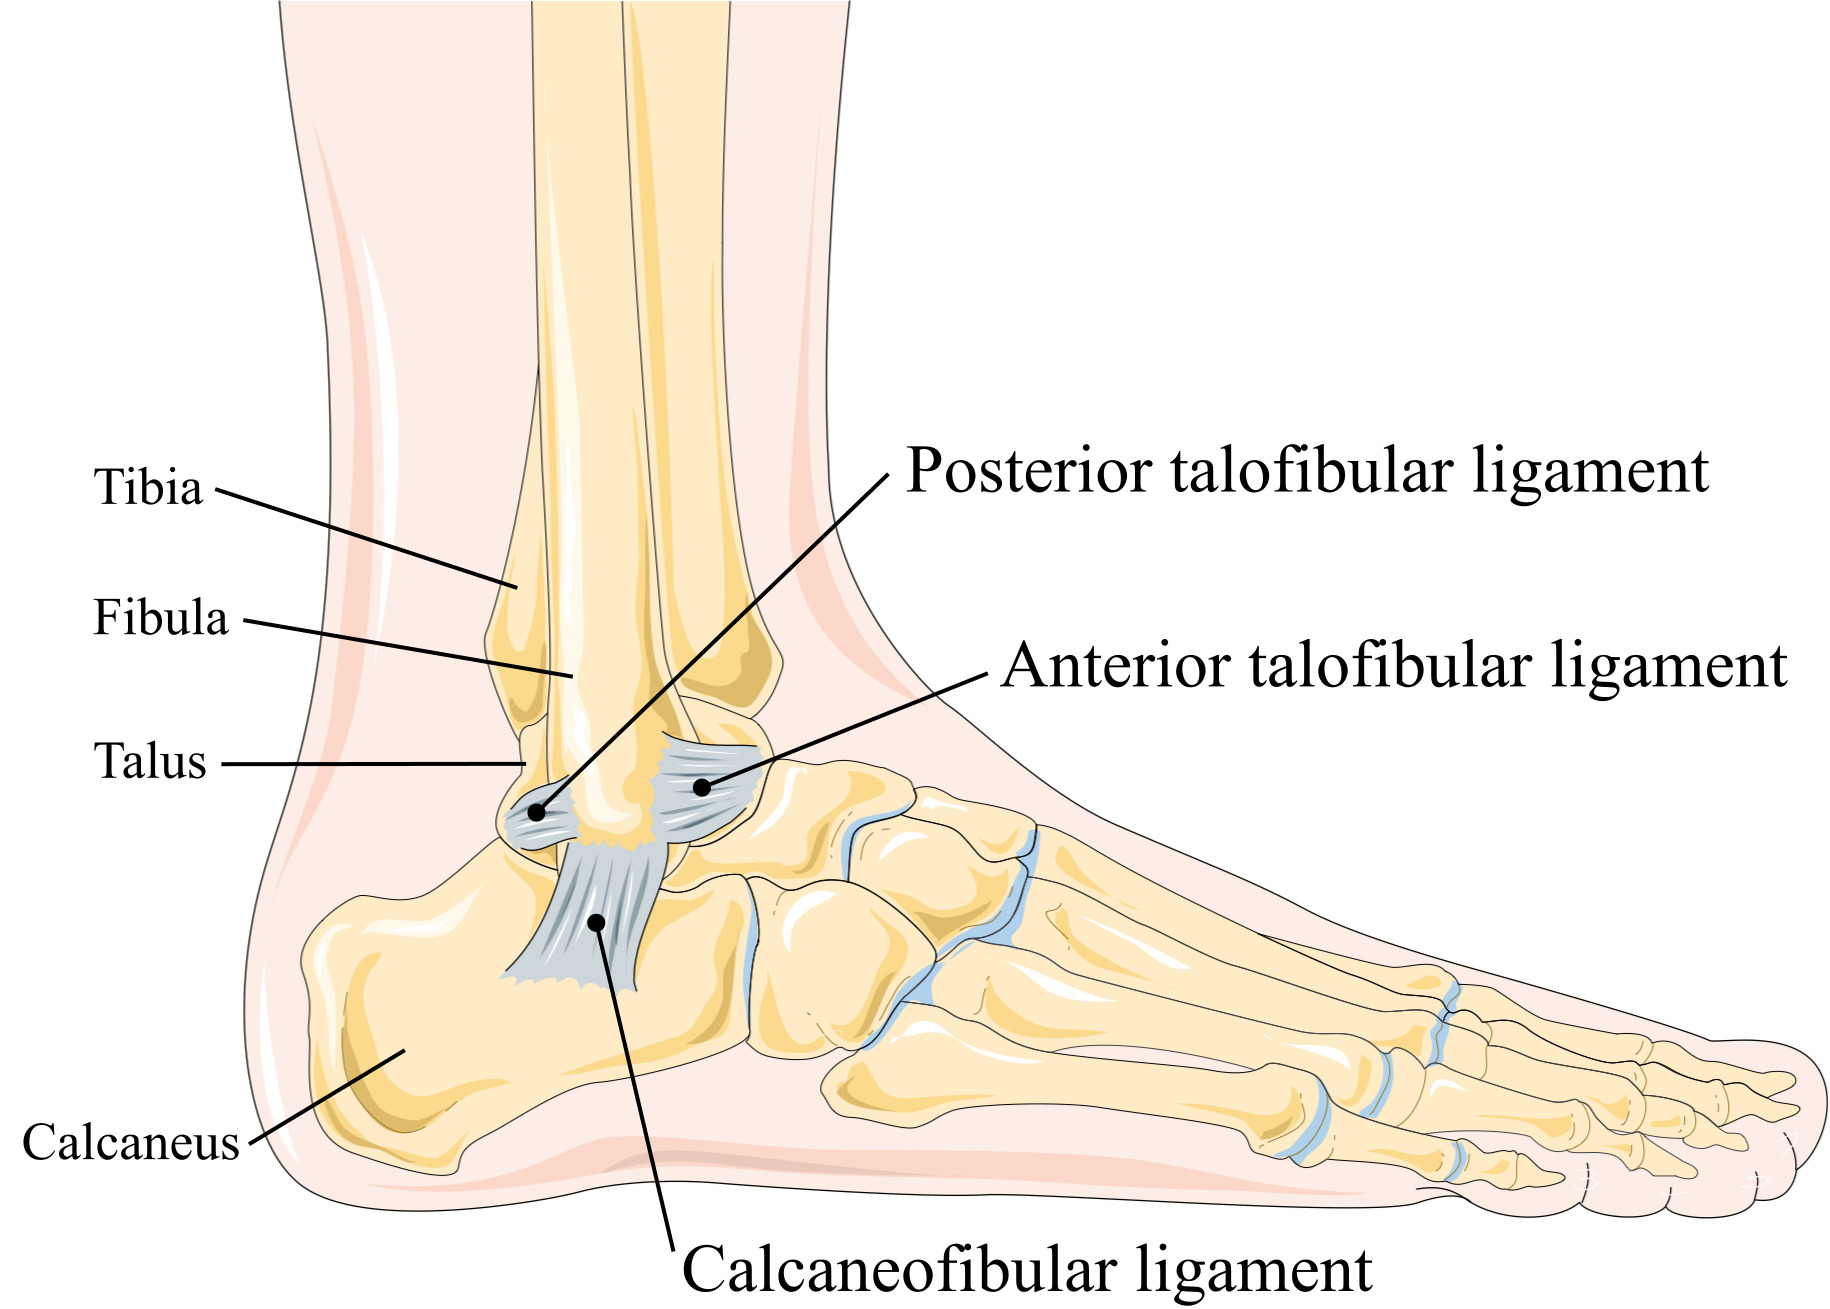

Sprained heel sale, Lateral Ankle Sprain Complete Physio sale

Lateral Ankle Sprain Complete Physio

Ankle Sprain